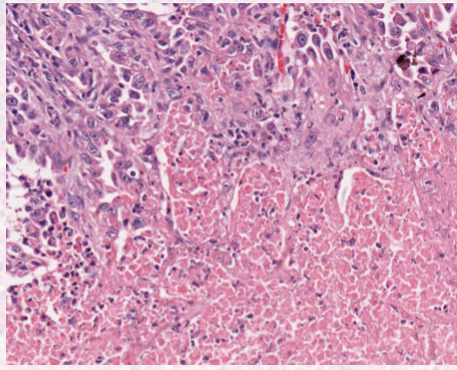

describe coagulative necrosis

protein denaturation

retention of cellular borders

ischemia

describe lytic necrosis

enzymatic digestion

loss of cell borders

neutrophil rich inflammation (bacterial)

Describe caseous necrosis

subtype of lytic necrosis

mycobacterial granulomas

describe liquefactive necrosis

end stage = fluid filled lesion.

final stages of necrosis in brain